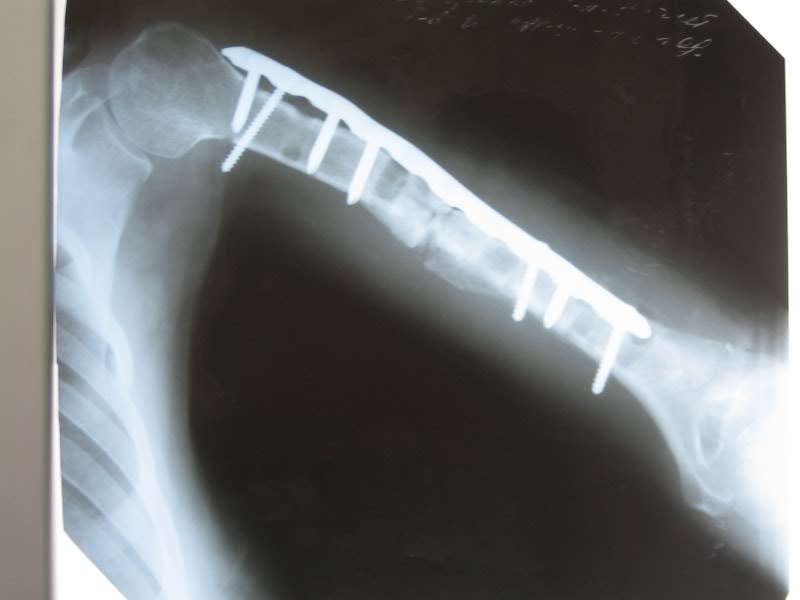

[Ortho] дефект-диастаз левой плечевой кости

п÷п╟я├п╦п╣п╫я┌п╨п╟ п╩п╣я┌ 40.

п■п╡п╟ пЁп╬п╢п╟ п╫п╟п╥п╟п╢ б═- п©п╣я─п╣п╩п╬п╪ п©п╩п╣я┤п╟.

п÷п╬я│п╩п╣п╢п╬п╡п╟я┌п╣п╩я▄п╫п╬ я│я┌п╟п╡п╦п╩п╦ я┌я─п╦ п©п╩п╟я│я┌п╦п╫я▀. п²п╟ п╡я│п╣ - п╬я┌я┌п╬я─п╤п╣п╫п╦п╣ п╪п╣я┌п╟п╩п╩п╟.

п║п╣п╧я┤п╟я│ - п╢п╣я└п╣п╨я┌-п╢п╦п╟я│я┌п╟п╥+я┐п╨п╬я─п╬я┤п╣п╫п╦п╣. п║я┐п╪п╪п╟я─п╫я▀п╧ п╢п╣я└п╣п╨я┌ п╬п╨п╬п╩п╬ 6 я│п╪. п■я▀я─п╨п╦ п╬я┌ п╡п╦п╫я┌п╬п╡. п≤п╫я└п╣п╨я├п╦п╦ п╫п╣я┌.